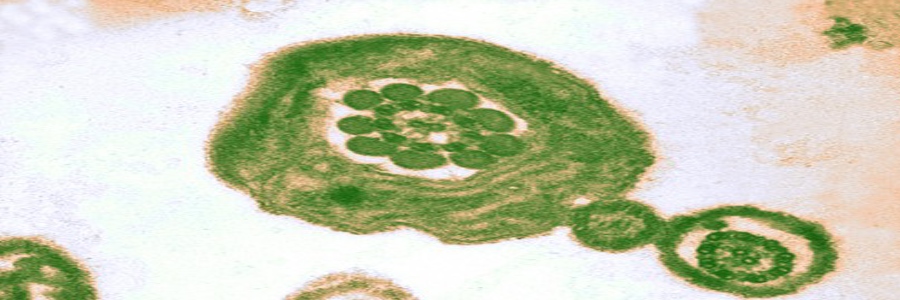

در این هفته بیشترین احتمال باردار شدن وجود دارد . چنانچه در زمان تخمک گذاری خود با همسرتان مقاربت جنسی بدون جلوگیری داشته باشید می توانید باردار شوید . بعد از خروج مایع منی ، میلیون ها اسپرم از درون واژن حرکت خواهند کرد و صدها اسپرم می توانند به سمت لوله فالوپ حرکت کنند جاییکه تخمک در انتظار است . به طور کلی یک اسپرم قادر خواهد بود به درون تخمک نفوذ کرده و در نتیجه باروری اتفاق می افتد . زمانیکه این اتفاق بیافتد شما باردار خواهید شد –اگرچه هنوز هیچ تغییری را در بدن خود حس نمی کنید.